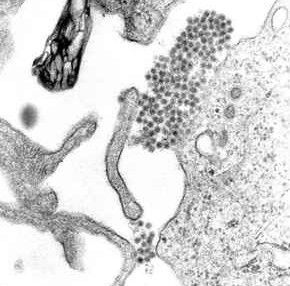

3. 1. 바이러스학

뎅기열 바이러스(DENV)는 ''플라비바이러스과'' ''플라비바이러스속''에 속하는 RNA 바이러스이다. 같은 속에는 황열 바이러스, 웨스트나일 바이러스, 지카 바이러스, 세인트루이스 뇌염 바이러스(St. Louis encephalitis), 일본뇌염 바이러스, 진드기 매개 뇌염 바이러스(Tick-borne encephalitis virus), 카사누르숲병 바이러스(Kyasanur forest disease), 옴스크 출혈열 바이러스(Omsk hemorrhagic fever) 등이 있다.[110] 이들 대부분은 모기나 진드기와 같은 절지동물에 의해 매개되므로, 아르보바이러스(절지동물 매개 바이러스)라고도 불린다.[110]

뎅기 바이러스의 유전체(유전 물질)는 약 11,000개의 뉴클레오타이드 염기로 구성되어 있다. 이 염기 서열은 바이러스 입자를 형성하는 세 가지 구조 단백질 분자(캡시드 단백질 C, 전구체 막 단백질 prM, 외피 단백질 E)와, 감염된 숙주 세포 내에서 바이러스 복제에 필요한 일곱 가지 비구조 단백질 분자(NS1, NS2a, NS2b, NS3, NS4a, NS4b, NS5)를 부호화한다.[29][30][111][112]

모기가 사람을 물면 타액과 함께 뎅기 바이러스가 피부로 들어간다.[47] 바이러스는 먼저 피부의 각질세포와 면역 세포인 랑게르한스 세포를 감염시킨다.[47] 바이러스는 랑게르한스 세포 표면의 DC-SIGN, CLEC5A 같은 C형 렉틴 및 만노스 수용체와 같은 막 단백질에 결합하여 엔도사이토시스라는 과정을 통해 세포 안으로 들어간다.[111] 특히 DC-SIGN 수용체가 주요 침입 경로로 여겨진다.[112]감염된 랑게르한스 세포는 가까운 림프절로 이동한다.[48][111] 세포 안으로 들어간 바이러스 게놈은 소포체에서 번역되어 새로운 바이러스 단백질과 RNA를 복제한다. 생성된 바이러스 입자는 골지체에서 성숙 과정을 거친 뒤, 엑소사이토시스를 통해 세포 밖으로 방출된다.[111] 이렇게 방출된 바이러스는 단핵구나 대식세포와 같은 다른 백혈구를 감염시키며[111] 온몸으로 퍼져나간다.[48]